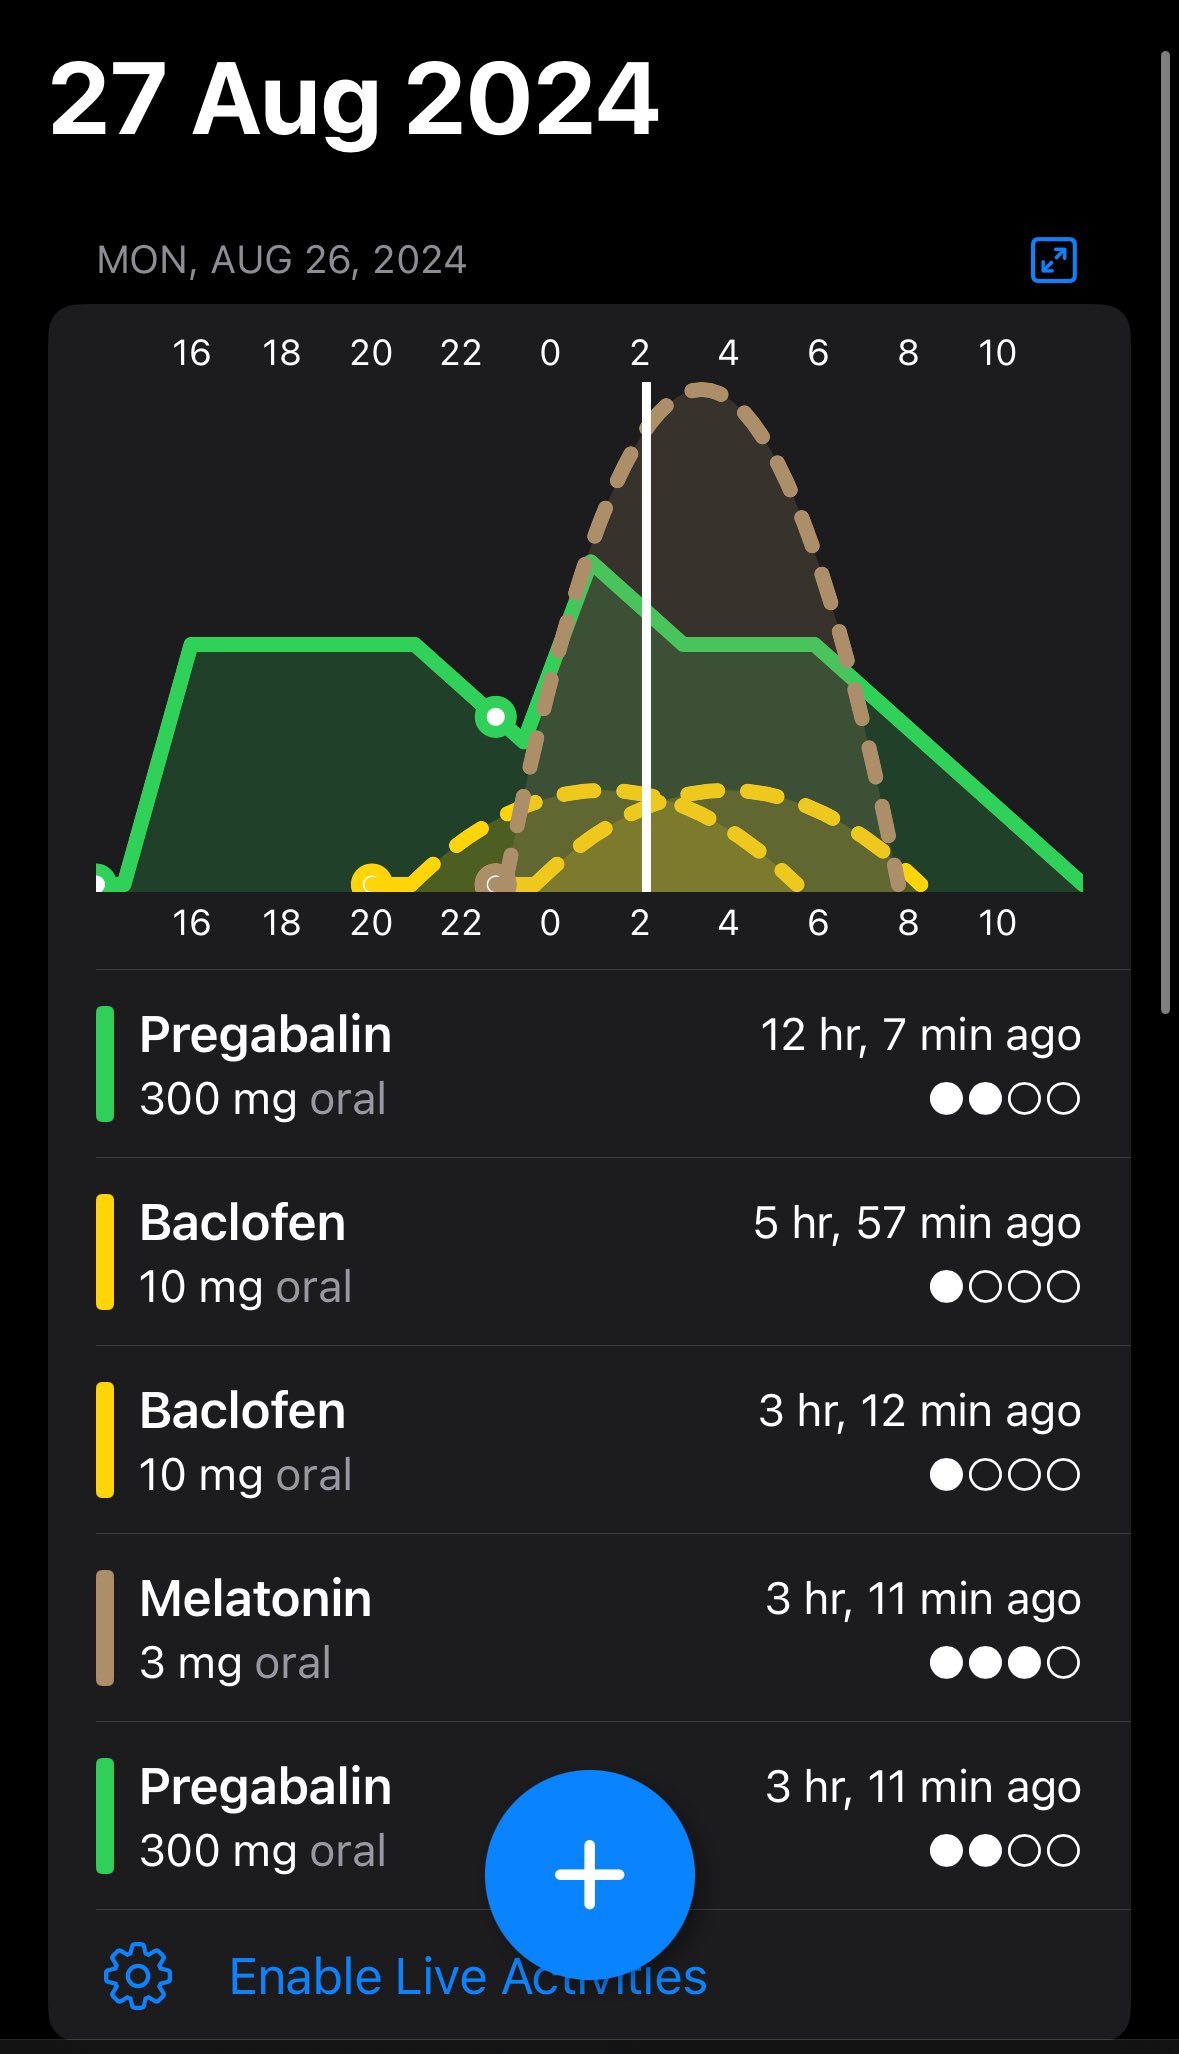

2024-08-14 11:34:53 UTC

甚至在第二天有余晖的感觉,虽然发生了很多破事但没怎么影响心情*抗焦虑&镇静

运动协调性稍差,表现为走路和站立时平衡不好

此剂量下对睡眠的改善作用,增加了慢波睡眠且没有影响rem,精力恢复+

FDA数据,在临床剂量下(75-600mg)普瑞巴林的依赖性低于bzd,并相比之下它产生的认知和精神运动障碍较轻 https://t.co/TJ7ZOQ7pbC